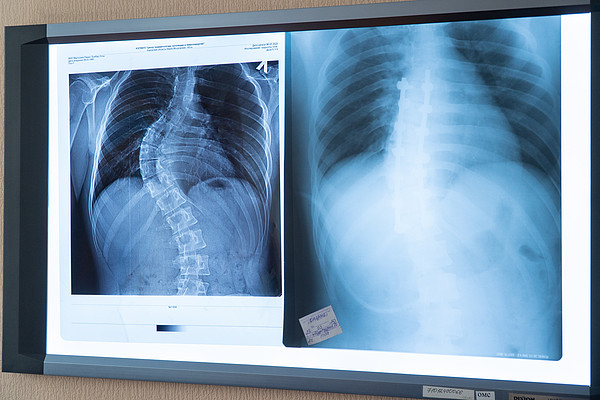

Файл:Nuss x-ray.jpg - Википедия

Клинический случай - применение операции по Нассу